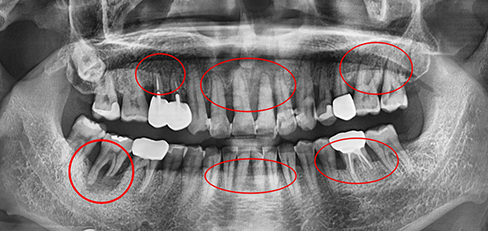

잇몸속 치아를 싸고 있는 치조골이 2/3 정도 소실되면

임플란트를 하고 그보다 치조골 손실이 적으면 비수술식

잇몸 치료를 통하여 자연치아를 최대한 살리려고 노력합니다.